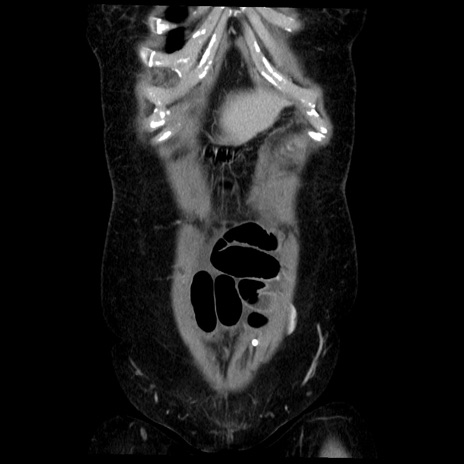

症例6(冠状断像)

【症例】50歳代女性

【主訴】下腹部痛

【既往歴】卵巣癌術後(8年前に当院で卵巣摘出)